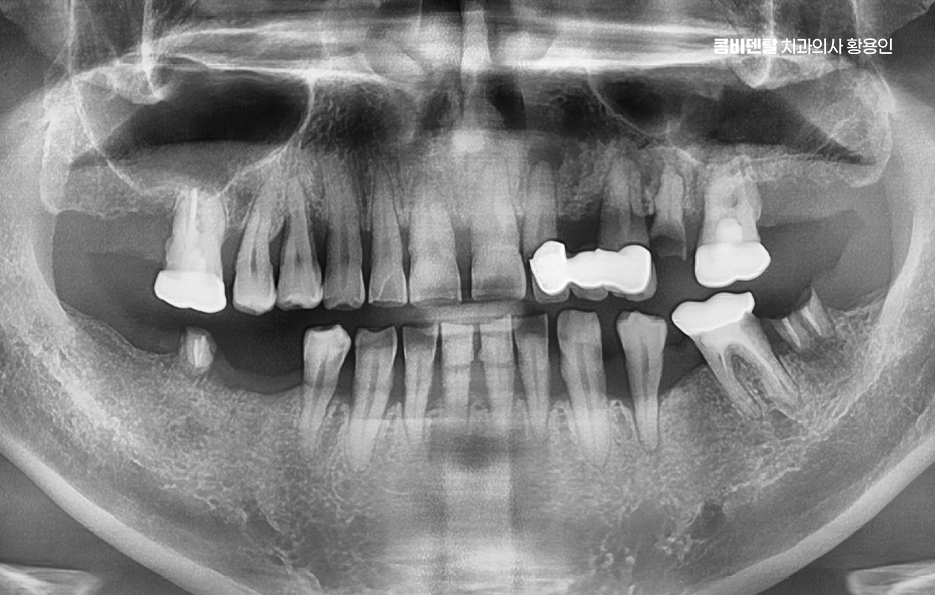

치아 발치 후 임플란트 치료 과정은 처음에 CT나 파노라마 엑스레이를 통해 뼈의 양과 밀도, 신경 위치를 정확히 확인하는 것부터 시작되며 치아가 빠진 자리에 뼈가 많이 흡수되어 있다면, 임플란트를 심기 전에 뼈이식을 먼저 해야 할 수 있지만 반대로 뼈 상태가 좋다면 임플란트를 심고, 보통 3개월 동안 뼈와 잘 붙을 때까지 골융합 과정을 기다리게 되며 골융합이 잘 이루어진 뒤에는 그 위에 지대주라는 연결 부품을 끼우고, 그 위에 최종 보철물을 씌우면서 치료가 마무리되고 있어요